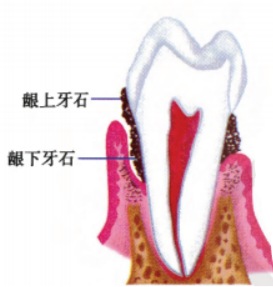

��ʯ�dz�����������������Ѹƻ������ڸƻ��ľ������������Һ������Һ�еĿ������������ɡ���ʯ�γɺ���ͨ���ճ�ˢ�����������ȼ�ͥ�ֶγ���ȥ������������רҵ���Ʋ������ճ���������Ԥ�����ٴ��γɡ���ʯ���ݳ����IJ�λ����������ԵΪ�磬�ɷ�Ϊ������ʯ��������ʯ��

��ʯһ���γɣ������Ρ�ճ�� �����ݱ��档���Ŀ��ᄃ������ݵ������ʡ������ʵȲ�λ����ܽ�ϣ������� ��Ƕ���� һ���������γ�Ȯ�ݽ�������Ƕʽ���ţ���Ҳ������ʯ���ѱ�������������ؼ����ǣ���ʯ�ı���ʼ�ջḲ����һ����ߣ���Ϊ��ǻϸ���� �������ء���